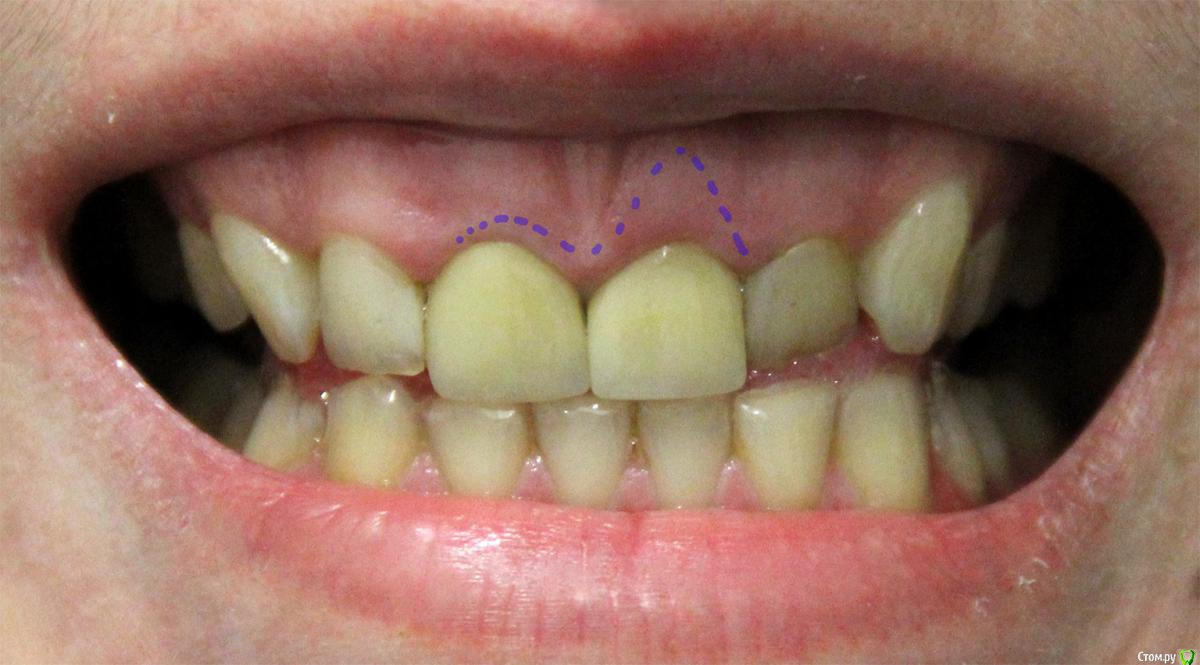

luma Опубликовано 11 апреля, 2016 Автор Поделиться Опубликовано 11 апреля, 2016 можете сделать фото?Вот фото прикладываю. Синим пунктиром выделила зону, откуда гной (или что там еще бело-зеленое может быть) удаляю. Ссылка на комментарий